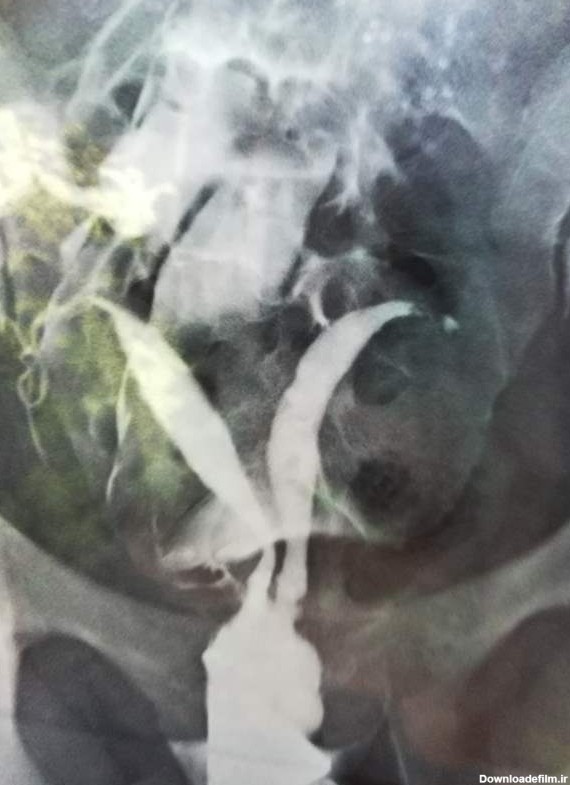

دوستان کسی میتونه عکسمو تفسیر کنه میوم و پولیپ چیه دیگه باعث ناباروری میشه؟تروخدا هرکس میدونه بگه کسی اینجوری بوده باردارشدین؟چیکار کردین😭😭

سلام دوستان من دیروز عکس رنگی رحم گرفتم ممنون میشم اگ کسی بلده برام تفسیر کنه خوبه که لوله سالمه

عکس رنگی رحم یا هیستروسالپینگوگرافی به معنای استفاده از اشعه ایکس برای مشاهده رحم و لولههای فالوپ است.